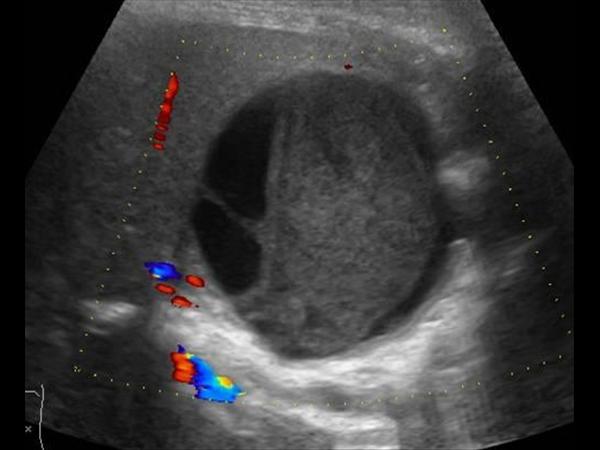

Chảy máu túi mật

» Thông tin: Nữ giới – 81 tuổi.

» Lâm sàng: Đau mạn sườn phải / Sau thủ thuật ERCP.